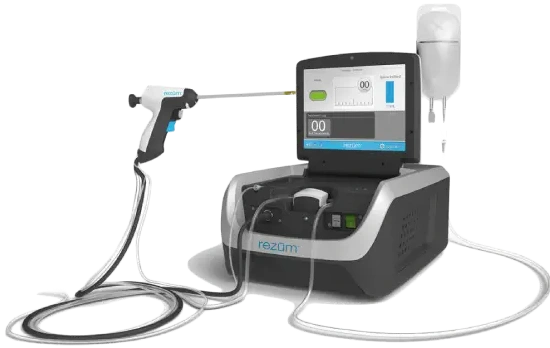

Rezum Water Vapor Therapy

We use steam energy to remove the enlarged part of the prostate within a few minutes of this process. This innovative therapy is available to all our patients at the Al Dhafra One Day Surgery Center Abu Dhabi, UAE. The whole procedure is to treat symptoms of urinary retention and obstruction.

Using steam to treat BPH (benign Prostatic hyperplasia) symptoms is beneficial for older and high-risk patients. This is the ideal alternative we offer at our one day surgery center instead of invasive surgery that may carry adverse effects on elderly patients.